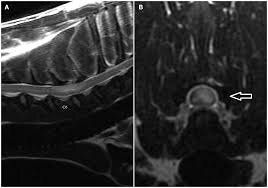

Ишемический инфаркт (типичный “паттерн”)

У кошек с предполагаемым острым инфарктом описаны очаги T1 iso/гипоинтенсивные и T2 гиперинтенсивные, иногда с мягким контраст‑усилением; при отсутствии другой системной патологии FCE рассматривается как вероятная этиология.

Для собак детально описаны МР‑находки у пациентов с предполагаемыми инфарктами/ишемической миелопатией и FCEM.

Важно: “нормальная МРТ” не исключает FCEM в первые сутки

Классическое клиническое знание, отражённое в обзорах, — МР‑изменения при FCE/FCEM могут быть минимальными или неочевидными в самые ранние сроки, что и объясняет интерес к DWI.